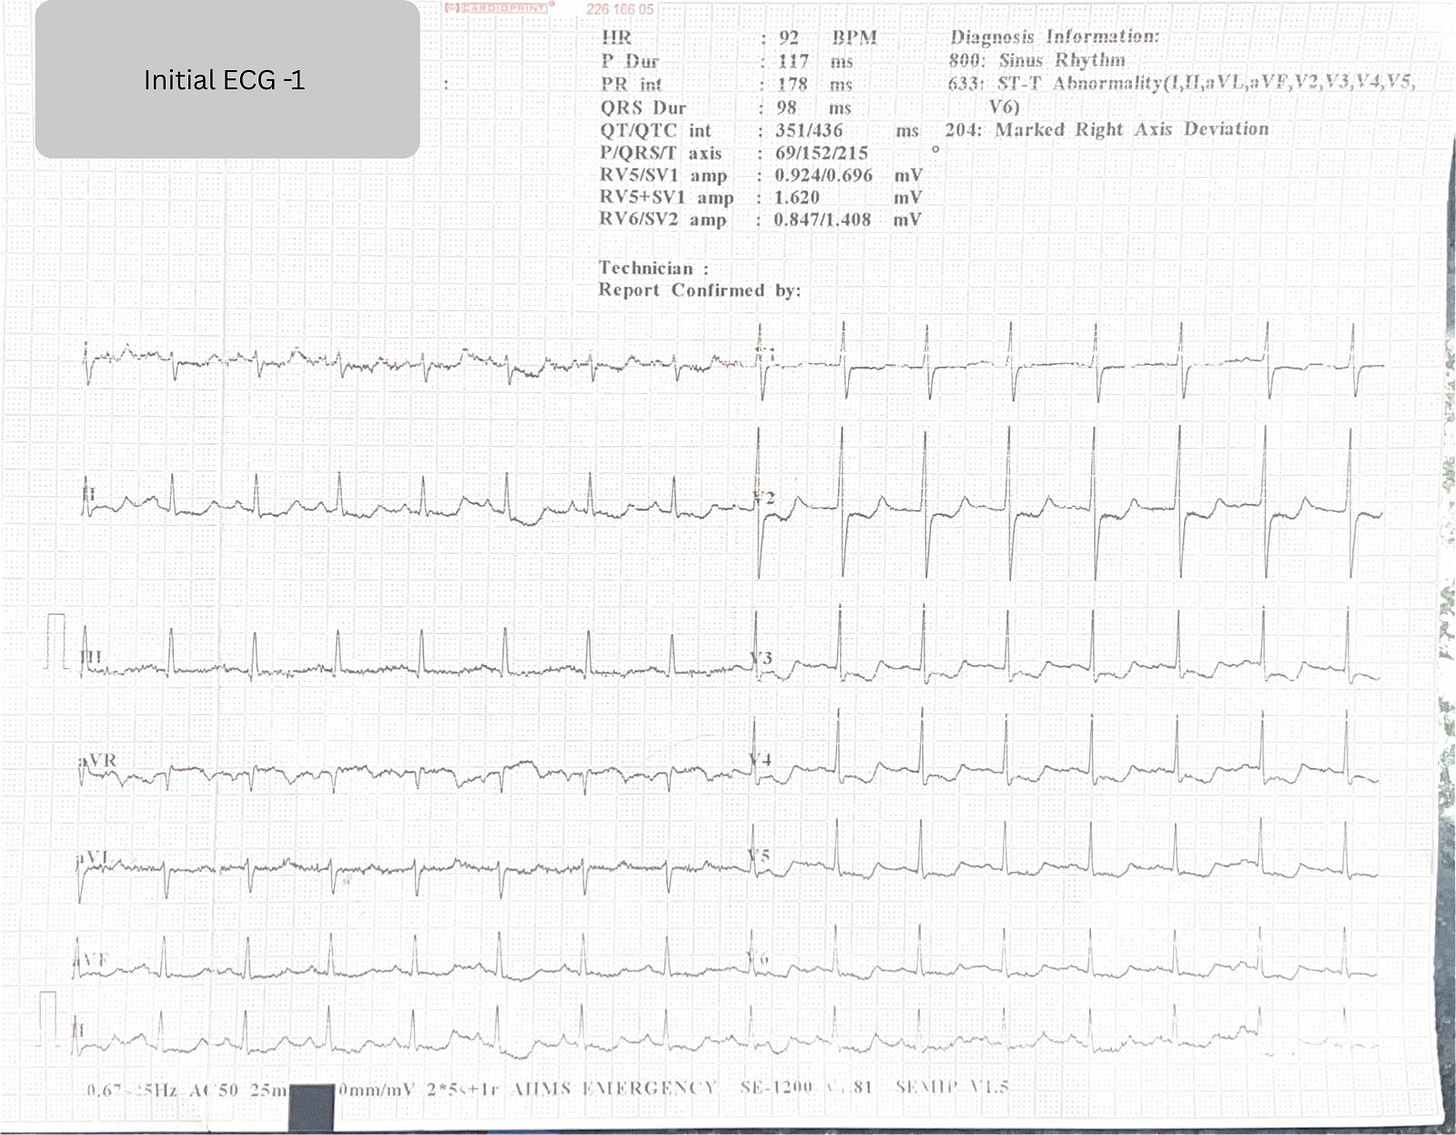

If you saw this ECG ,

aVR ST elevation.

V1 ST Segment elevated in comparison to V2.

Diffuse ST depression.

New right axis deviation.

your first instinct would probably be left main or proximal LAD occlusion.

ECG 1 was taken shortly after this massive blood loss.

ECG 1: The Concerning Findings

The initial ECG showed:

aVR ST elevation

V1 > V2 ST segment level

Diffuse ST depression

New right axis deviation (Lead I isoelectric/negative vs. ECG 2)

This pattern is alarming because it mimics:

Proximal LAD occlusion

Left main disease

Severe multivessel ischemia